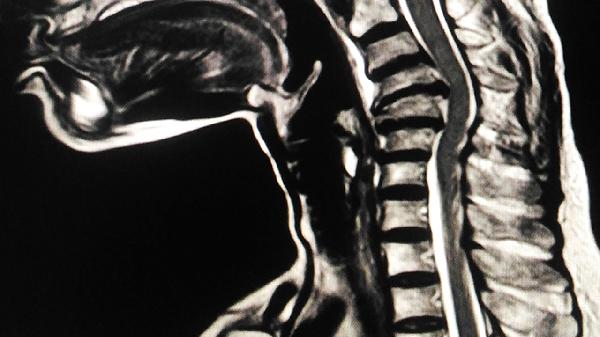

急性发作时,往往有感冒或腹泻等全身炎症症状,脊髓损伤症状突然发作,几小时至几天发展到高峰,受影响的平面更加清晰,易于发现,四肢大多是弛缓性麻痹,常伴有感觉和括约肌功能障碍,脑脊液白细胞增多,主要是单核细胞和淋巴细胞,蛋白质含量也略有增加。如果细菌的原因主要是中性白细胞增多,脑脊液中的蛋白质含量也会显著增加。磁共振成像可以显示脊髓水肿病变,髓内异常信号,可以增强。

疾病的发作是阴险的,早期症状通常是逐步的局部隔离感觉障碍、萎缩和手部小肌肉无力。病变主要见于下颈椎和上胸椎,也延伸至延髓。脑脊液检查通常是正常的。磁共振成像可以看到延髓的长T1和长T2信号。